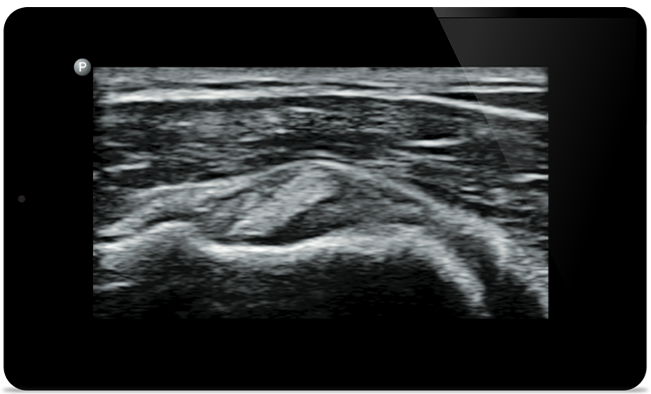

Padstatic case example image

Start treatment with an accurate diagnosis

Start treatment with an

accurate diagnosis

Lumify helps you see the fine details in muscles, joints, ligaments, tendons and cartilage to make a more accurate diagnosis of injuries.